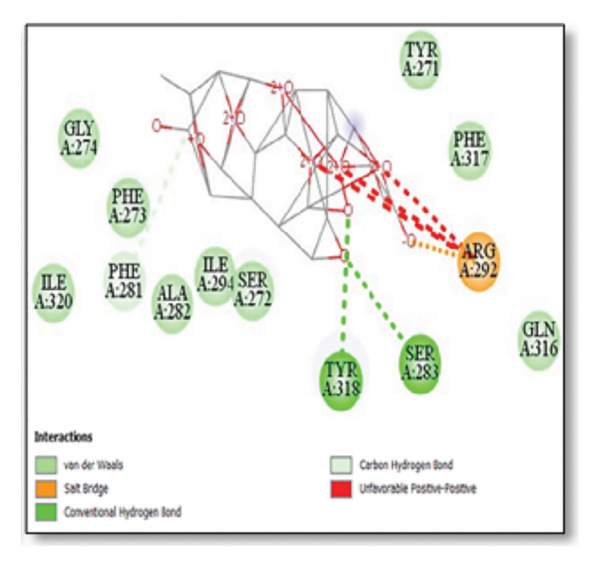

For the tau protein repeat domain, ginkgolide recorded a strong binding energy of −10.63 kcal/mol, with a key stabilizing interaction involving HIS329. This interaction was characterized by a D–A distance of 3.05 Ǻ and an excellent angle of 170.04°. Other top binding compounds included ginsenosides (−6.28 kcal/mol), also interacting with HIS329 and PRO364, and galantamine (−5.47 kcal/mol), forming bonds with VAL337 and VAL339. Berberine bound at −5.33 kcal/mol via GLN351. Apigenin exhibited favorable interaction with the tau repeat domain via a hydrogen bond with ILE 328 (D–A: 2.91 Ǻ; angle 161.21°), highlighting the high quality of the interaction. Among the reference drugs, donepezil bound at −5.34 kcal/mol. Figure 5 details the binding characteristics for tau protein.

Figure 7Molecular docking analysis of ginkgolide interactions with Alzheimer’s disease‐related proteins: Molecular docking analysis of ginkgolide’s interactions with four key proteins—sortilin, clusterin, amyloid‐beta peptide, and tau protein. Column (a, d, g, j) shows the receptor–ligand interaction surface, providing a visual representation of how ginkgolide binds to the active site of each protein. The second column (b, e, h, k) depicts the secondary structure and ligand interactions, offering insights into the specific amino acid residues and structural motifs convoluted in binding. The third column (c, f, i, l) presents the LigPlot+ interaction diagram, providing a 2D schematic of the ligand–protein interactions, highlighting hydrogen bonds and hydrophobic contacts between ginkgolide and the surrounding amino acids of the binding site.(a)(b)(c)(d)(e)(f)(g)(h)(i)(j)(k)(l)

Multiplatform docking (MTi‐AutoDock, DockThor, and Webina) and PLIP analysis confirmed consistent binding orientations and affinities. Key interactions (H‐bonds, hydrophobic contacts) aligned with known active‐site residues. Redocking RMSD values (< 2 Å) indicated high pose reproducibility. Binding‐site validation confirmed biologically relevant cavities.